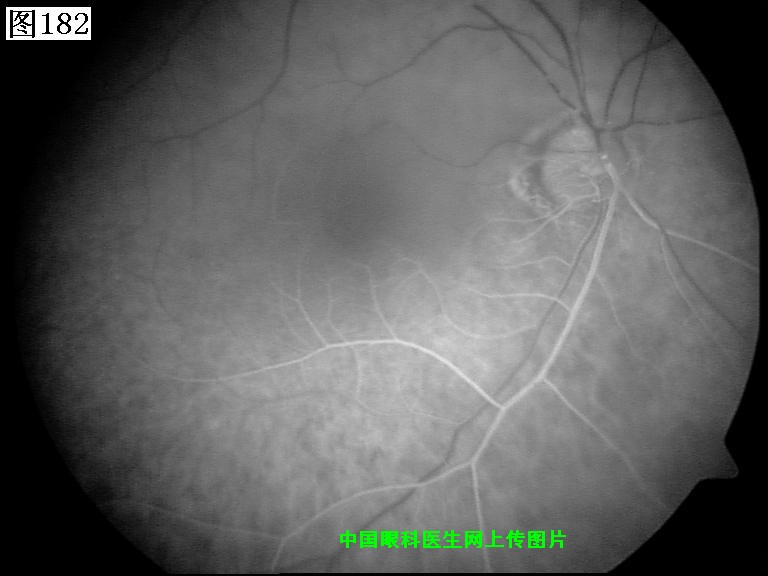

181 182 183 184